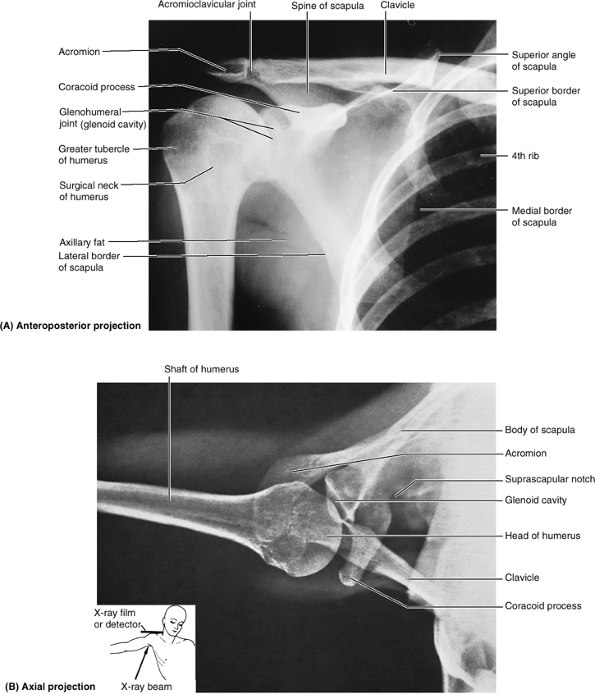

or dislocation) or malformation (Fig. SA6.1).

(suprasternal notch). The acromial end of the clavicle often rises

higher than the acromion, forming a palpable elevation at the acromioclavicular (AC) joint.

The acromial end can be palpated 2–3 cm medial to the lateral border of

the acromion, particularly when the arm is alternately flexed and

extended. Either or both ends of the clavicle may be prominent; when

is easily felt and often visible. The superior surface of the acromion

is subcutaneous and may be traced medially to the AC joint. The lateral

and posterior borders of the acromion meet to form the acromial angle (Fig. SA6.1B). Inferior to the acromion, the deltoid muscle forms the rounded curve of the shoulder. The crest of the scapular spine is subcutaneous throughout and easily palpated.

-

Superior angle of the scapula lies at the level of the T2 vertebra.

Medial end of the root of the scapular spine is opposite the spinous process of the T3 vertebra.

Inferior angle of the scapula lies at the

level of the T7 vertebra, near the inferior border of the 7th rib and

7th intercostal space.